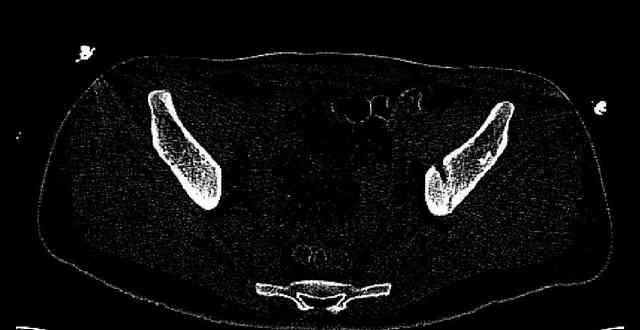

The last two images from the 3-D CT scan certainly makes the fracture look worse than the plan radiographs.

Some more images. Does it help to guess which part of the acetabulum is displaced?

Normal appearing SI joints and a healed posterior column limb... my bet's on caudal segment displacement.